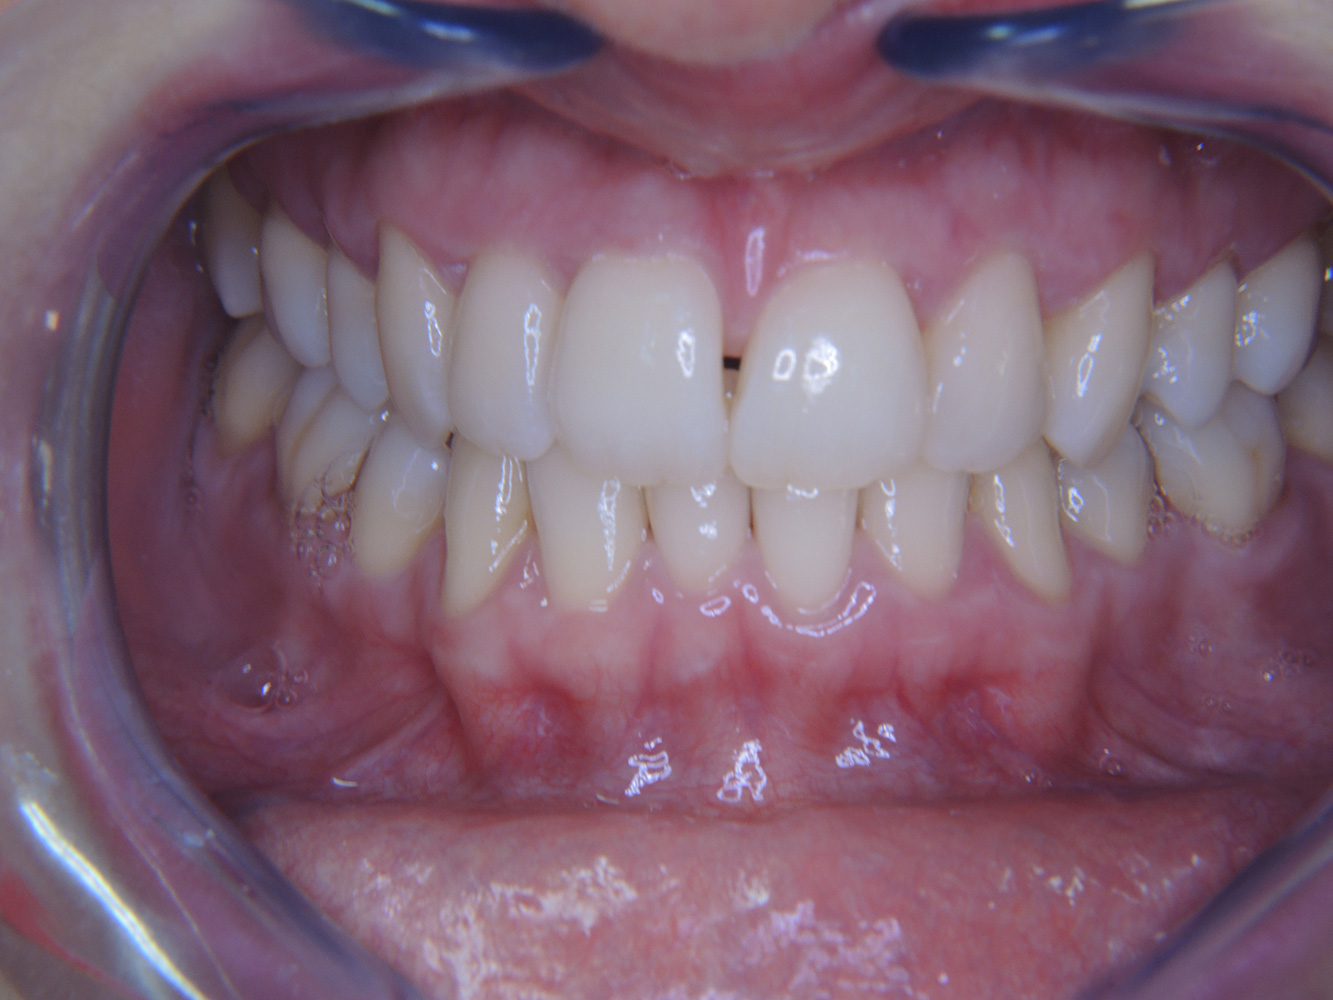

Patientenfälle nach IPCUm das Zusammenspiel der für den IPC definierten Bedarfs- und Risikofaktoren sowie die Auswirkungen einzelner Faktoren zu illustrieren, dienen nachstehende Fallbeispiele*. Die mundgesunde DiabetikerinEine 51-jährige mundgesunde Diabetikerin stellt sich zur Präventionssitzung vor. Die Blutzuckerwerte sind stabil bei einem HbA1c = 6,2%, folglich gilt sie mit dem entsprechenden Medikament Metformin (Antidiabetikum) als suffizient eingestellt. Die Patientin hat keine bestehenden Versorgungen oder orale Vorerkrankungen. Anhand der aktuellen Befunde lässt sich eine Gingivitis bei sonst stabilem parodontalem Zustand (Stage II, Grad B) feststellen. mehr Infos Fallpräsentation: Management komplexer ZahnprothetikEs ist längst bekannt, dass Mundgesundheit und Allgemeingesundheit in direktem Zusammenhang stehen und einen zum Teil bidirektionalen Einfluss aufeinander haben. Die Berücksichtigung beider Faktoren sind bei der Planung der oralen Prävention und Therapie der Patienten in der Zahnarztpraxis unabdingbar. Dabei ist oberstes Ziel, die Gesundheit und die Lebensqualität der Patienten sowohl aus zahnmedizinischer -und medizinischer Sicht zu erhalten. mehr Infos Der (mund)-gesunde Patient mit ImplantatenDer 55-jährige Patient gibt in der Anamnese an, keine Allgemeinerkrankungen zu haben und keine Medikamente einzunehmen. Die Lebensgewohnheiten des Patienten sind ebenfalls unauffällig. Der Patient hat einige zahnärztliche Restaurationen und zwei Implantate (2. und 4. Quadrant). Anhand der aktuellen Befunde lässt sich eine Gingivitis bei stabilem parodontalen Zustand am reduzierten Parodont (Stadium III, Grad A) feststellen. mehr Infos Der gesunde Patient mit parodontaler Vorerkrankung & PeriimplantitisEin 52-jähriger Patient stellt sich zur Präventionssitzung vor. Der Patient hat keine Allgemeinerkrankungen und nimmt keine Medikamente ein. Er hat verschiedene zahnärztliche Versorgungen und zudem zwei aktive kariöse Läsionen. Außerdem verfügt der Patient über vier Implantate (2., 3. und 4. Quadrant). Es zeigt sich eine parodontale Vorerkrankung (Stadium IV, Grad B). Derzeit herrschen stabile parodontale Verhältnisse, lediglich am Implantat regio 36 zeigen sich Sondierungstiefen (ST) von 5 mm. Zudem lässt sich eine Gingivitis feststellen. mehr Infos Der Diabetiker mit ParodontitisDieser Fallbericht eines 52-jährigen Mannes mit Typ-2-Diabetes und Parodontitis hebt hervor, wie durch individuelle Vorsorgemaßnahmen, die Gesundheit des Zahnhalteapparates erhalten bzw. das Fortschreiten der Erkrankung kontrolliert werden kann. mehr Infos Der 28-jährige Raucher mit ZahnerosionenDieser Fallbericht eines 28-jährigen Rauchers mit Zahnerosionen zeigt die Bedeutung personalisierter Patientenprofile. Er unterstreicht die Notwendigkeit, sowohl die Mundgesundheit als auch die allgemeine Gesundheit zu berücksichtigen, um Erkrankungen der Zähne bzw. des Zahnhalteapparates effektiv zu verhindern. mehr Infos Der Endokarditis-Patient mit aktiven KariesläsionenDer Patient ist 39 Jahre mit Z.n. Herzklappenersatz wegen Klappenfehlers und Endokarditis. Als Antikoagulans (Gerinnungshemmer) wird regelmäßig ASS 100 eingenommen. Aus dem Bereich Lebensstil ist die Ernährungsweise als kariesfördernd einzustufen, da mit hoher Regelmäßigkeit zuckerhaltige Lebensmittel sowie sechs bis sieben Mahlzeiten täglich verzehrt werden. Die Mundgesundheit des Patienten zeigt ein mittleres Kariesrisiko mit aktiven Läsionen. Das Parodontitisrisiko ist niedrig, es besteht eine Gingivitis. Es ergeben sich folgende Empfehlungen für die Prophylaxebehandlung. mehr Infos Die gesunde Patientin mit parodontaler VorerkrankungDie 68-jährige Patientin hat keine zahnmedizinisch relevanten allgemeingesundheitlichen Vorerkrankungen oder Medikation, auch aus dem Lebensstil ergibt sich kein besonderes Risiko. Die Patientin hat zwei Implantate (3. Quadrant, seit fünf Jahren) sowie eine parodontale Vorerkrankung (Parodontitis Stadium IV, Grad B) mit Zahnverlust. Derzeit zeigen sich stabile parodontale Verhältnisse. Für die Prophylaxesitzung ergeben sich vier Empfehlungen in den Bereichen Anamnese/Befund, Motivation/Instruktion, der Wahl der geeigneten Instrumente und für Resümee/Folgetermin. mehr Infos